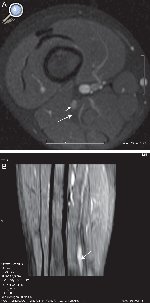

La neoplasia más común y descrita en la bibliografía es el tumor de la vaina neural periférica (PNST)33, 34, 35. La importancia de poder diferenciar en imágenes entre los tumores benignos como el neurofibroma y neurilemoma o schwanoma, radica en que el schwanoma puede resecarse sin afectar al nervio, porque está contenido dentro de la misma cápsula, el epineuro y, habitualmente pueden separarse quirúrgicamente. Por el contrario, el neurofibroma debe ser resecado con parte del nervio porque el tumor no puede ser separado de sus fibras. Ambos tumores han sido ampliamente estudiados y descritos en trabajos de RM. En un estudio de 52 pacientes que analizaron las diferencias en las imágenes ponderadas en T2, el signo de la diana (58 vs. 15%), el realce central (75 vs. 8%) y una combinación de ambas (63 vs. 3%) se presentaron principalmente en los neurofibromas. Por el contrario, los hallazgos sugestivos de neurilemomas fueron la apariencia fascicular, un anillo delgado hiperintenso en T2, una combinación de ambos (8% neurofibromas vs 46% neurilemomas) y el realce difuso. Los grandes neurilemomas sufren con frecuencia cambios degenerativos que incluyen quistes, hemorragias y fibrosis36 (Figura 5).

Figura 5. Niño de 4 años con marcha polineurítica de un año de evolución, con EMG compatible con lesión del nervio peroneo. A) Secuencia SPGR ponderada en T1 con saturación de la grasa e inyección de gadolinio. Muestra un nódulo en la división peronea del nervio ciático (flecha corta). Por detrás se observa la división tibial con un patrón fascicular normal (flecha larga). B) Reconstrucción MPR curva donde se observa el engrosamiento fusiforme en el tercio distal del nervio ciático (flecha).